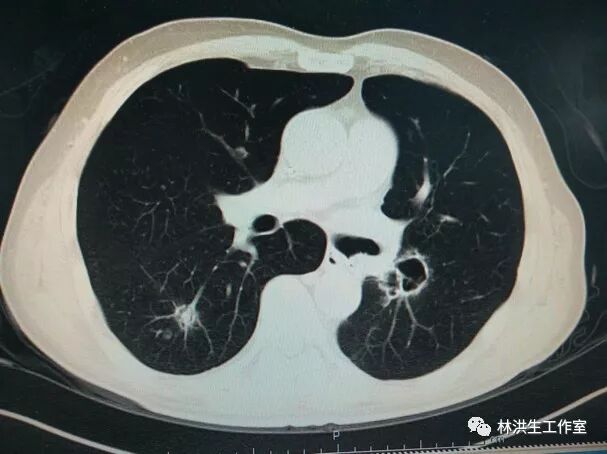

2016-11-28

2017-10-21中药治疗后:双肺多发转移瘤大者增大至约2.6*2.3cm